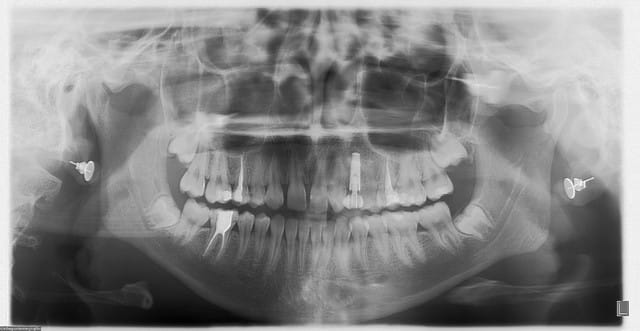

allez...suite des gammes...entre deux "regards" sur doctissimo...(on se marre bien...Sid est déchaîné...)

bon , patiente 60ans...pas de pbs médicaux...paro...moyenne mais pas trop mal stabilisée...y a mieux...c'est sûr...(j'entends déjà les "foudres" de Noah...)

os type 3...pas top...d'où compression/expansion...

3 implants posés en 36, 37, et 15...

les implant en 15 et 36 sont des 4.7mm par 11.5mm et l'implant en 37 est un 3.7mm par 10mm (pas assez de place au niveau proth pour 2 4.7mm...)

juste un ptit problème de dernière minute pour l'implant en 37...l'expansion finale de l'implant mis en 36 a un peu fissuré la crête...me faisant perdre un peu de stab primaire...rien de dramatique...mais j'ai préféré du coup enfouir...

j'avais oublié...la pano...

pour les photos, c'est mieux...pas encore Yann Arthus Bertrand...mais là çà peut aller...on progresse, on progresse...